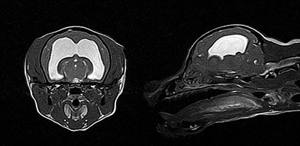

강아지 MRI

강아지 MRI는 반려동물의 신경계 질환이나 뇌, 척수, 관절 등의 정밀 진단에 매우 유용한 영상 검사입니다. 주로 경련, 사지마비, 뇌염, 뇌종양, 디스크 질환, 수두증 등 신경계 증상이 있을 때 시행하며, 방사선을 사용하지 않고 강한 자기장을 이용해 신경 조직의 변화를 상세하게 볼 수 있습니다. 검사 시 강아지를 전신마취해야 하며, 마이크로칩 같은 금속성 물질이 있으면 제거 후 촬영하는 것이 좋습니다.

- 뇌종양은 MRI에서 뇌 내에 명확한 종괴(종양 덩어리)가 보이며, 조영제 주입 후 해당 부위가 강하게 증강되는 특징이 있습니다. 종양 주변에 부종이나 뇌조직 압박 증상이 동반돼 보이며, 위치와 크기가 확인됩니다. 뇌종양은 노령견에서 발작과 함께 행동 변화, 균형 장애, 시각장애 등의 신경학적 증상이 나타납니다.

- 반면 간질 자체는 구조적 이상을 동반하지 않는 특발성 간질일 경우 MRI에서 이상 소견이 없거나 미약한 변화를 보입니다. 그러나 구조적 간질의 경우에는 뇌염, 뇌 손상, 뇌기형, 뇌출혈 등 뇌 조직에 국소적 변화가 MRI에 나타나기도 합니다. 간질 증상은 반복적 경련이 주로 특징이며, MRI를 통해 간질의 원인이 되는 뇌 조직 손상 여부를 평가합니다.

결론적으로, MRI는 뇌 안에 실제 종양 덩어리 및 주변 조직 변화를 뚜렷이 보여주며, 간질은 뇌종양과 달리 종괴 없이 경련 발생 원인에 따른 뇌 조직 변화를 확인하는 데 도움을 줍니다. 따라서 MRI 영상 소견과 임상 증상을 종합해서 뇌종양과 간질을 구분하고, 이에 맞는 치료 계획을 세우게 됩니다.